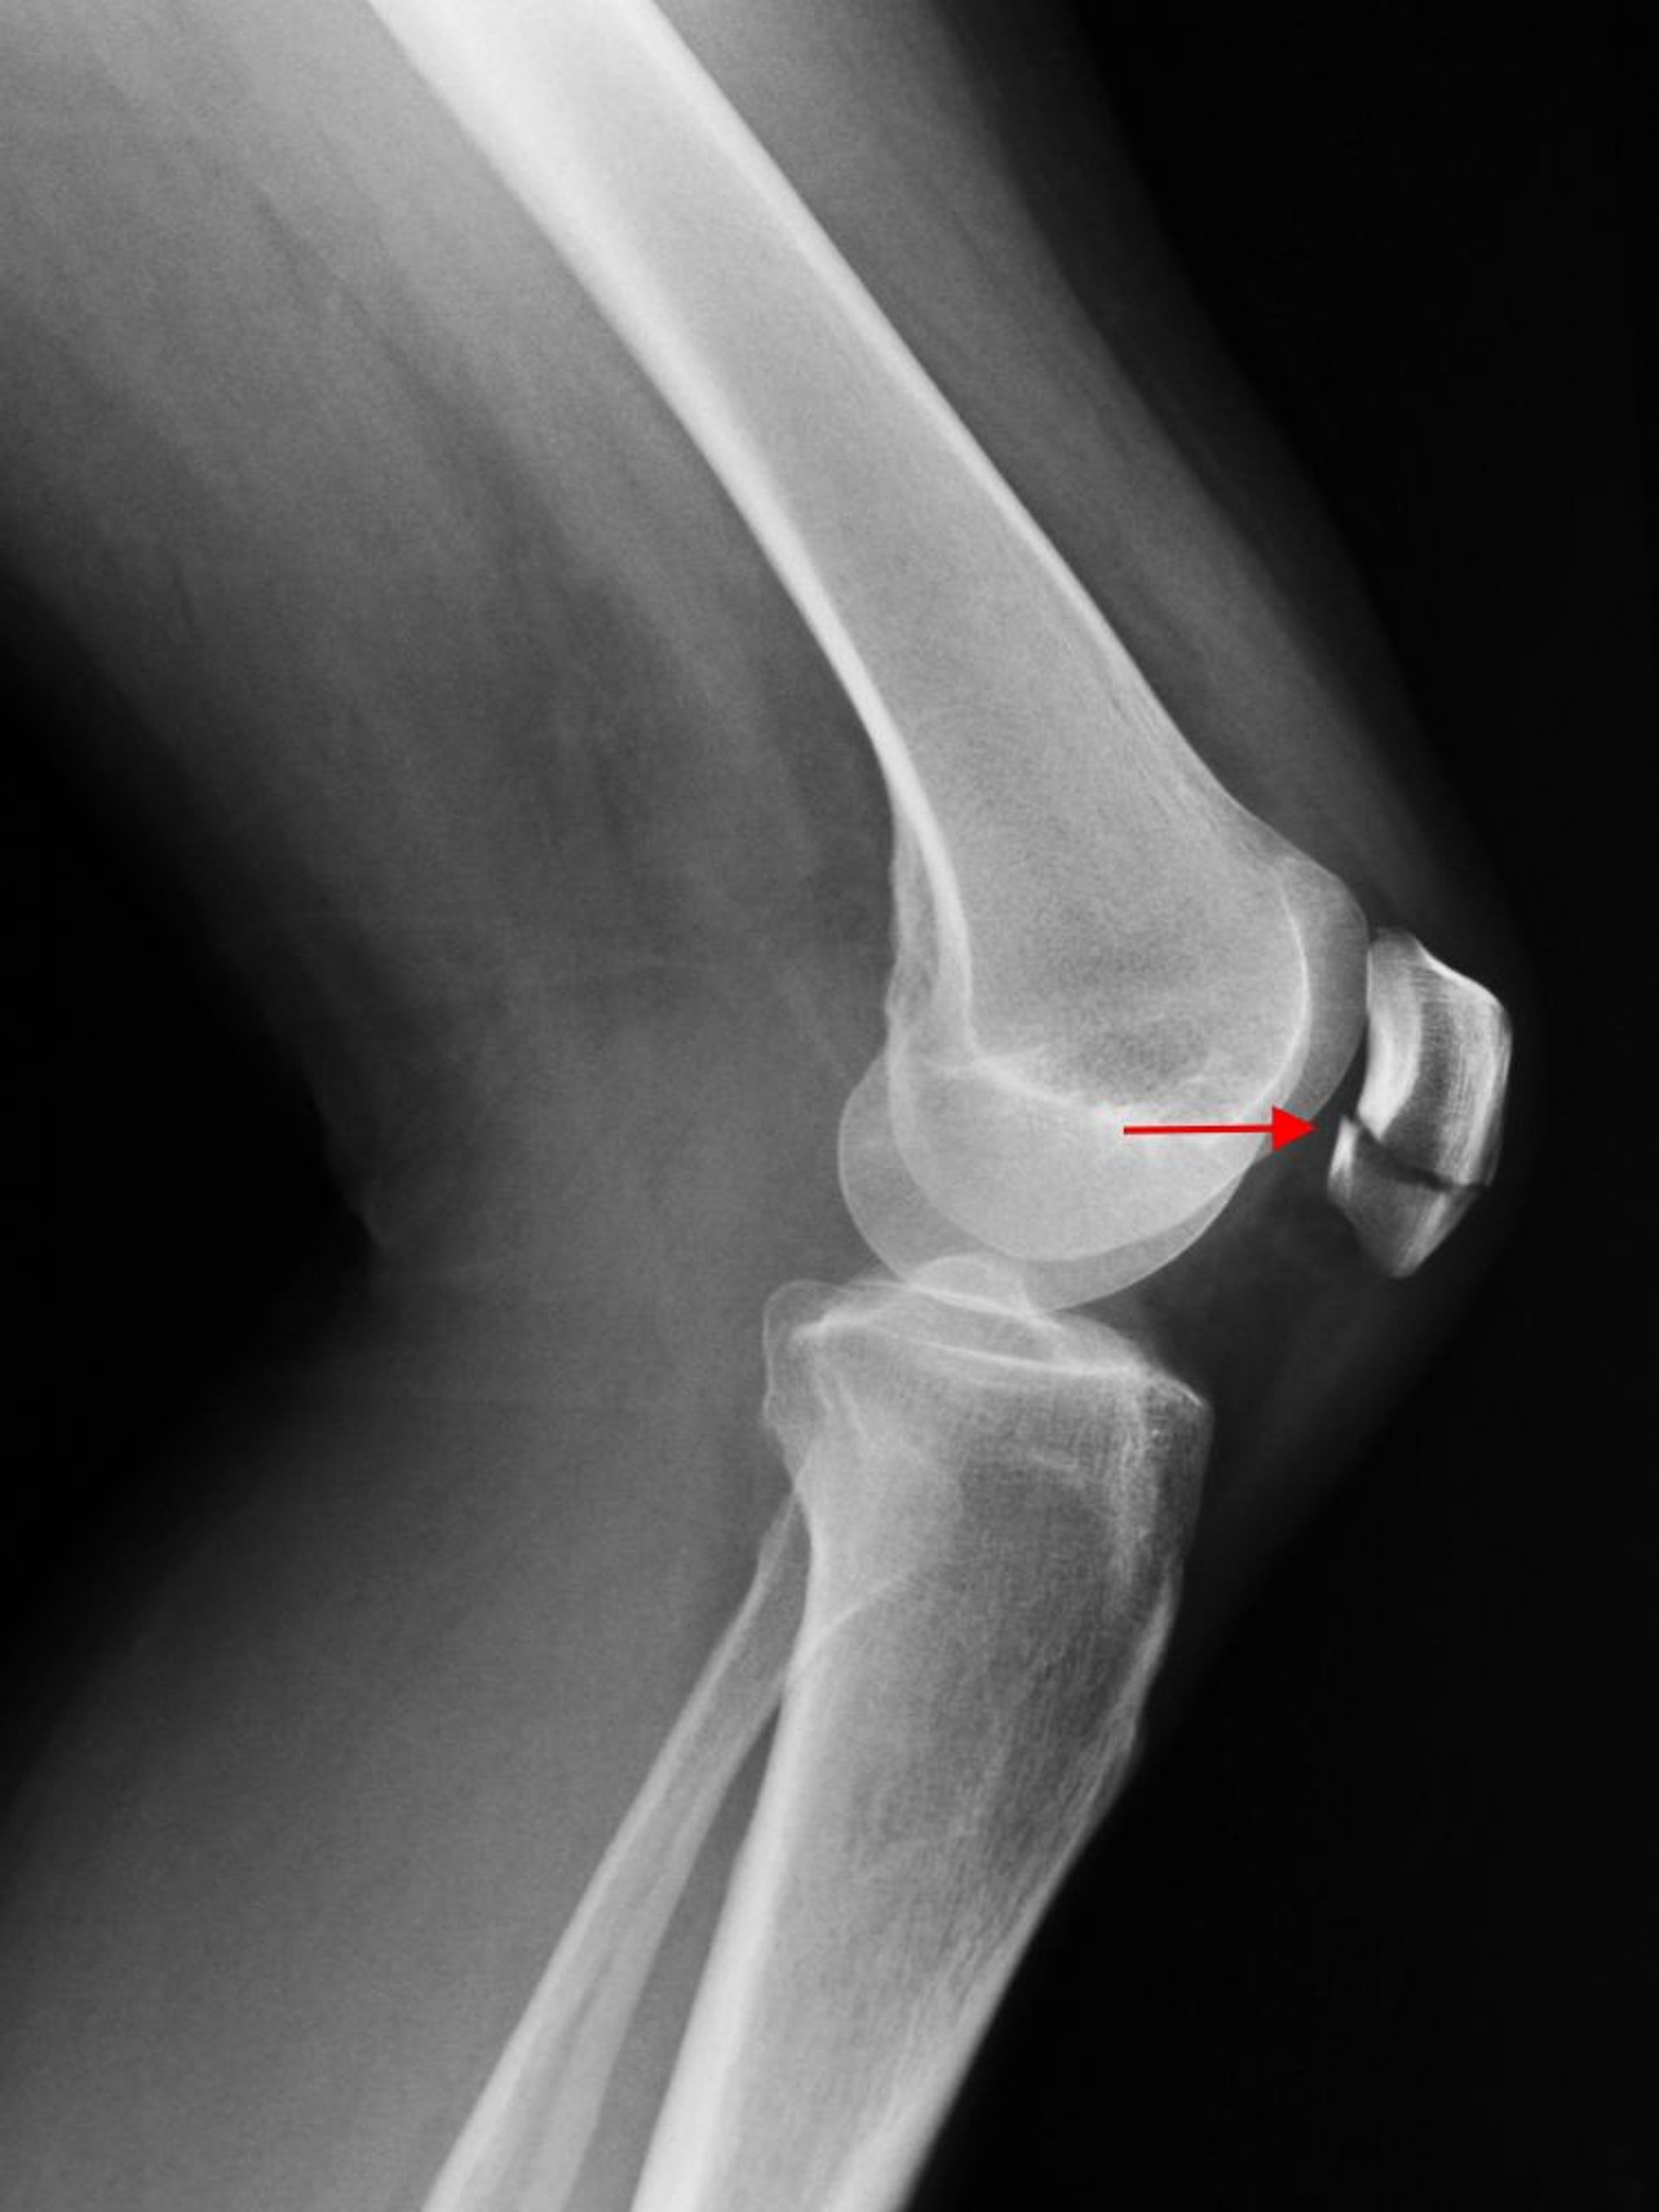

Una radiografía lateral de rodilla muestra una fractura transversal de la rótula (flecha).